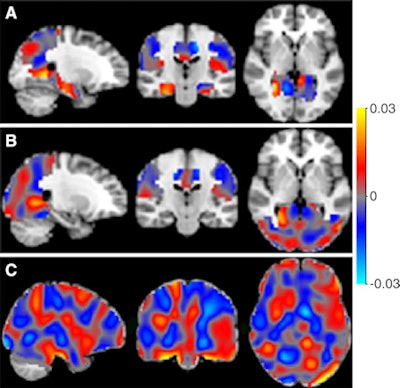

The classifiers can be represented as discrimination maps, where red indicates that the intensity at that location contributes to the likelihood of the images belonging to the more-advanced stage, and blue to the likelihood of belonging to the less-advanced stage. A: Alzheimer's disease (AD) vs. SCD; B: AD vs. MCI; and C: MCI vs. SCD. Image courtesy of RSNA.The researchers then analyzed images using an open-access software platform, Pattern Recognition for Neuroimaging Toolbox (Pronto), which enables multivariate analysis of neuroimaging data based on machine learning.

The Pronto application was able to differentiate between individuals with Alzheimer's disease, MCI, and SCD, the researchers reported. It was also able to predict the prognosis of patients with accuracy ranging from 82% to 90%, leading Wink et al to conclude that ASL is a "promising alternative functional biomarker" for the early diagnosis of Alzheimer's disease.